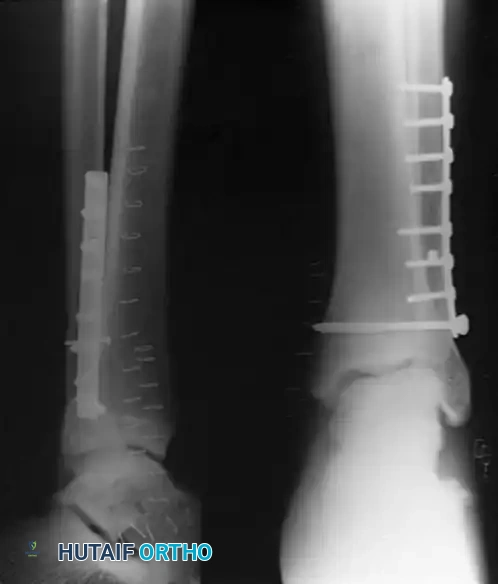

Image

FIGURE 54-5: Bimalleolar ankle fracture featuring an oblique fracture of the lower fibula treated with interfragmentary screw fixation. Kirschner wires were utilized for the internal fixation of the medial malleolus.